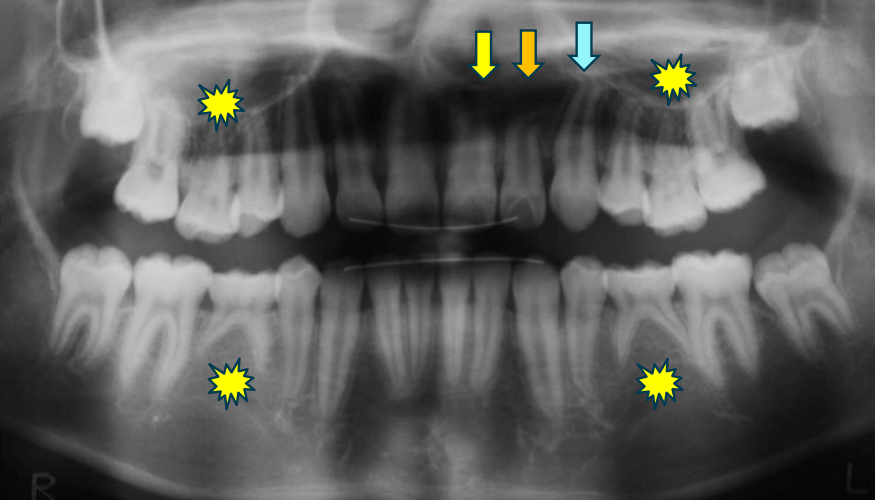

| 年齢・性別 | 8歳11ヶ月の男児 |

|---|---|

| 主訴 | 上顎の永久歯の位置がおかしいとのことで来院。萌出していない右上の前歯の状態に不安を抱えられていました。 |

| 治療期間・回数 | 約3年2ヶ月 |

| 費用 | 440,000円(税別) |